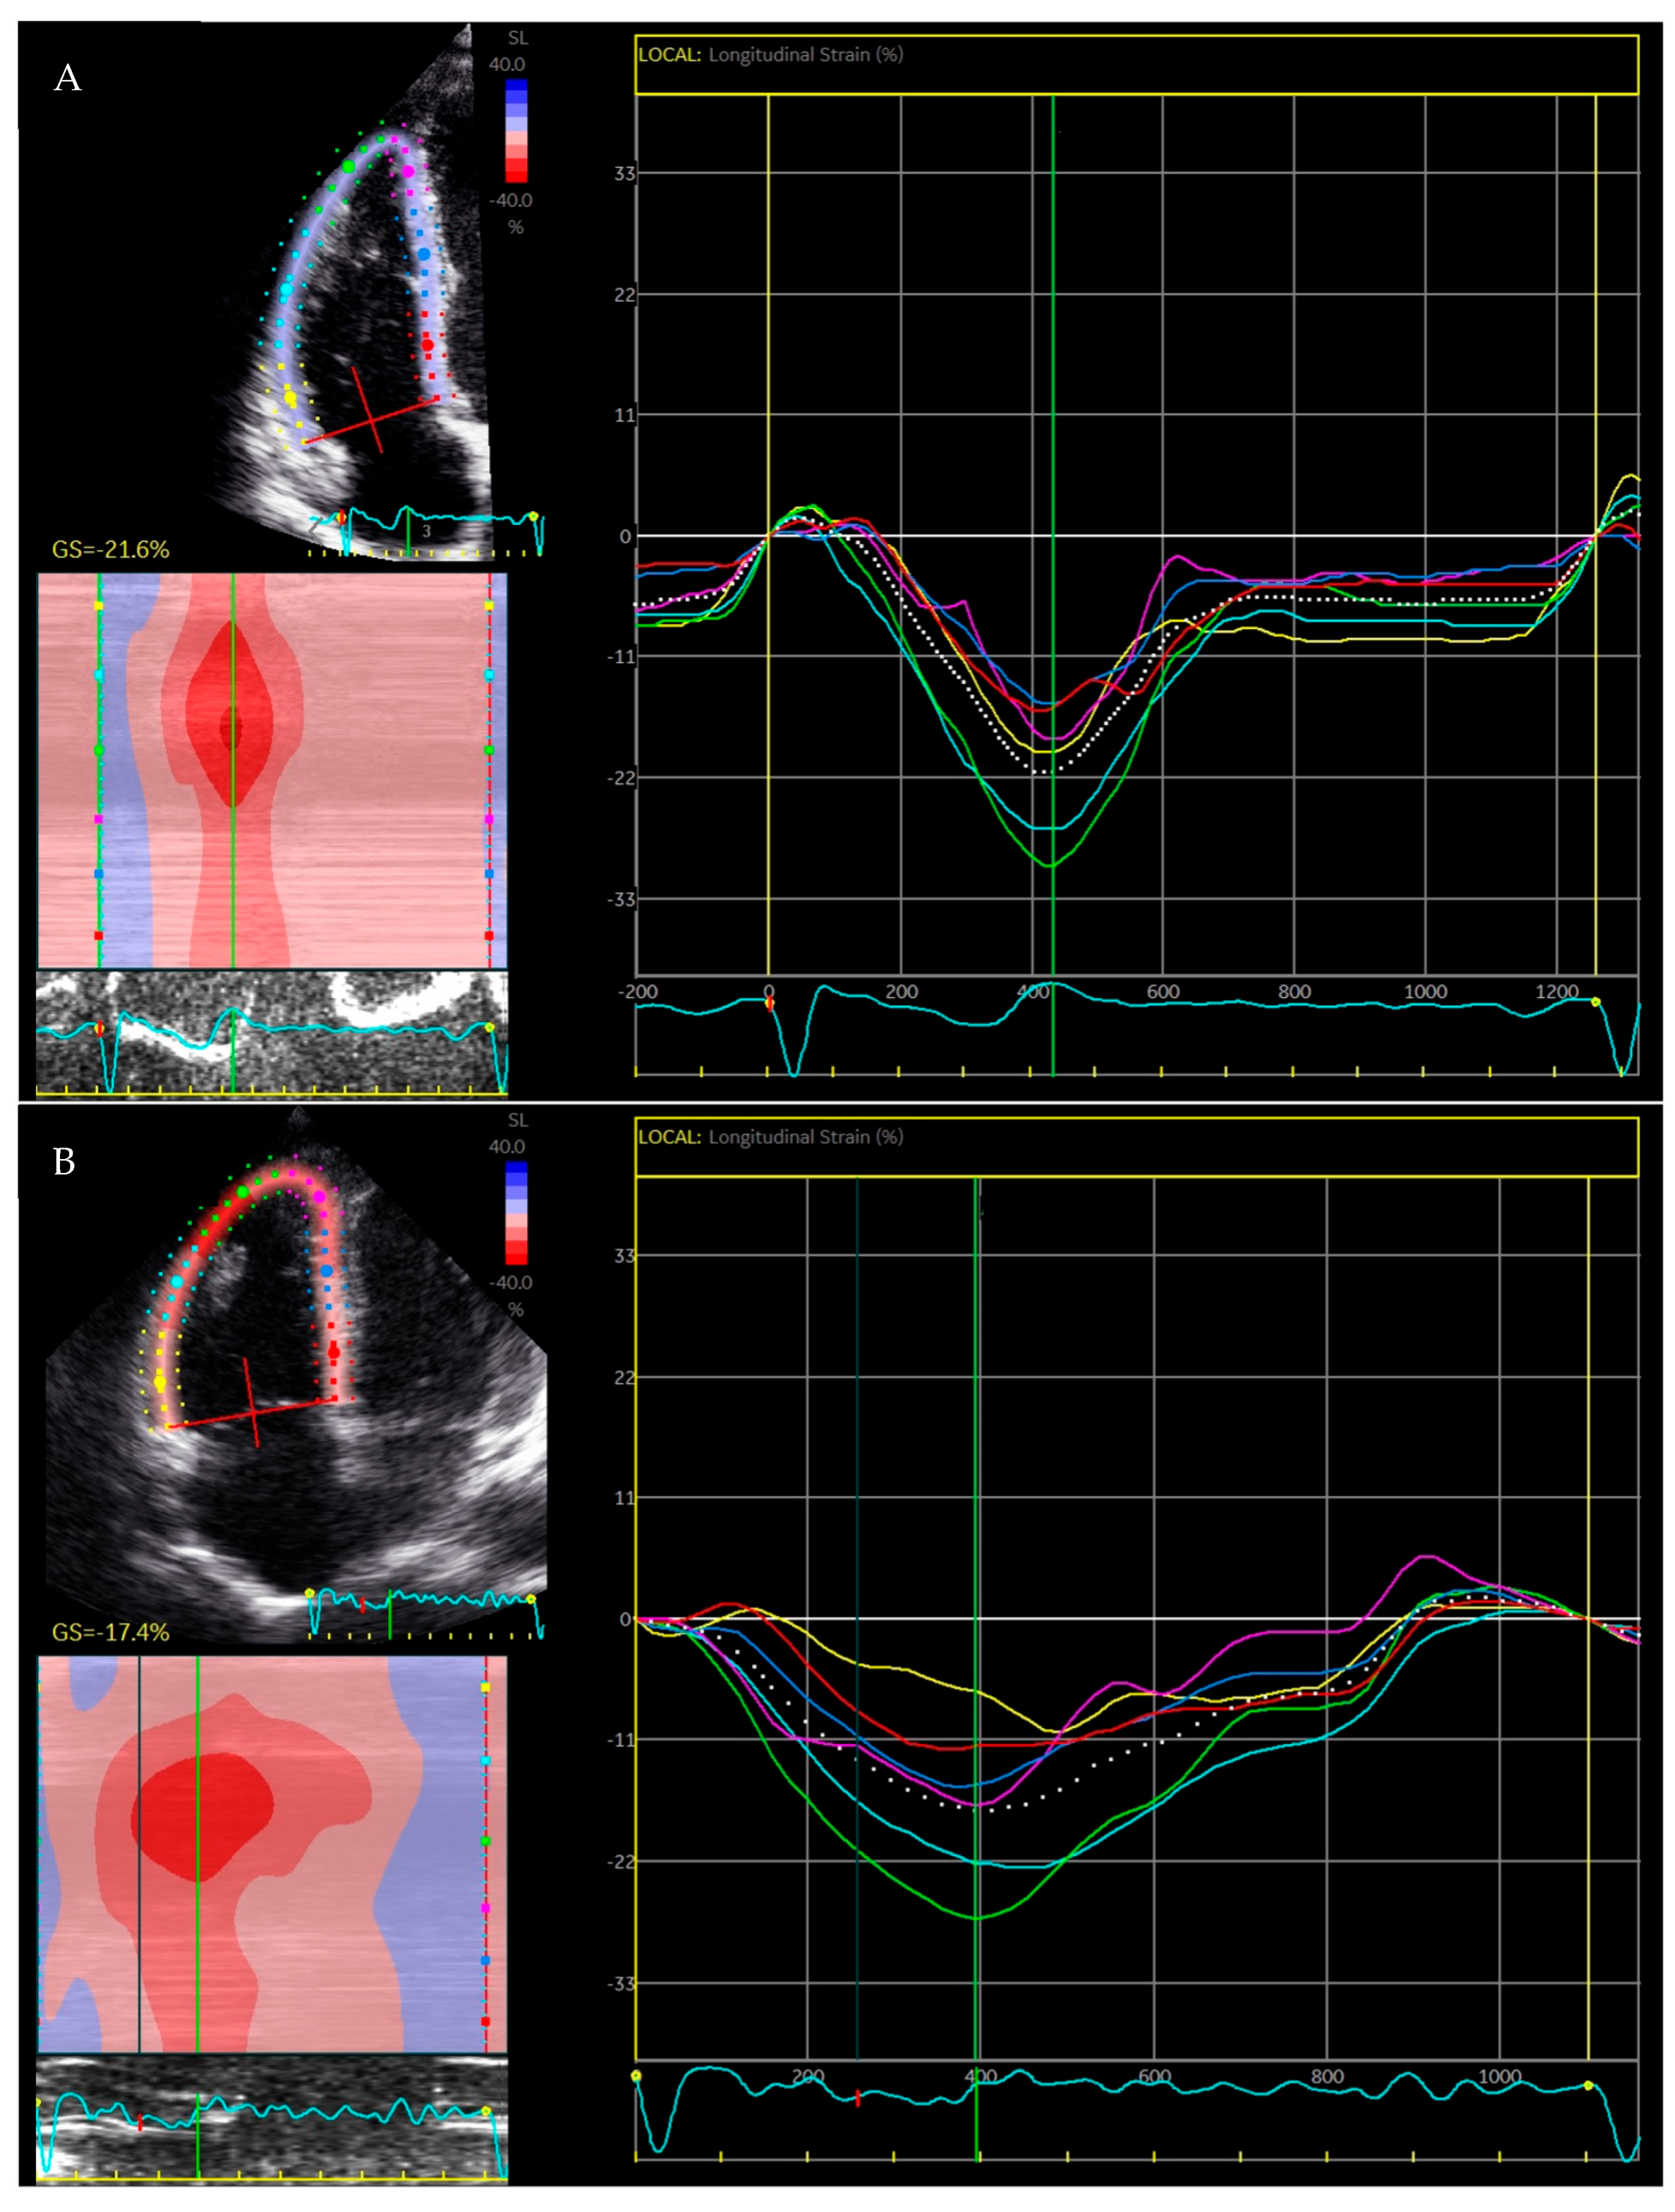

2.2. Right Ventricular Strain

3.2. Regional Strain

3.3. Mechanical Dispersion